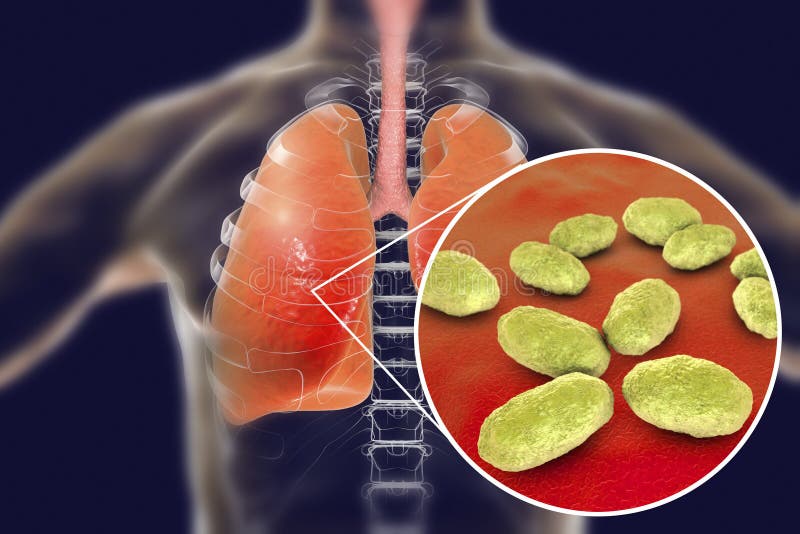

Фотографии бактерий, вызывающих бактериальные пневмонии у животных

Раздел: Другие животные